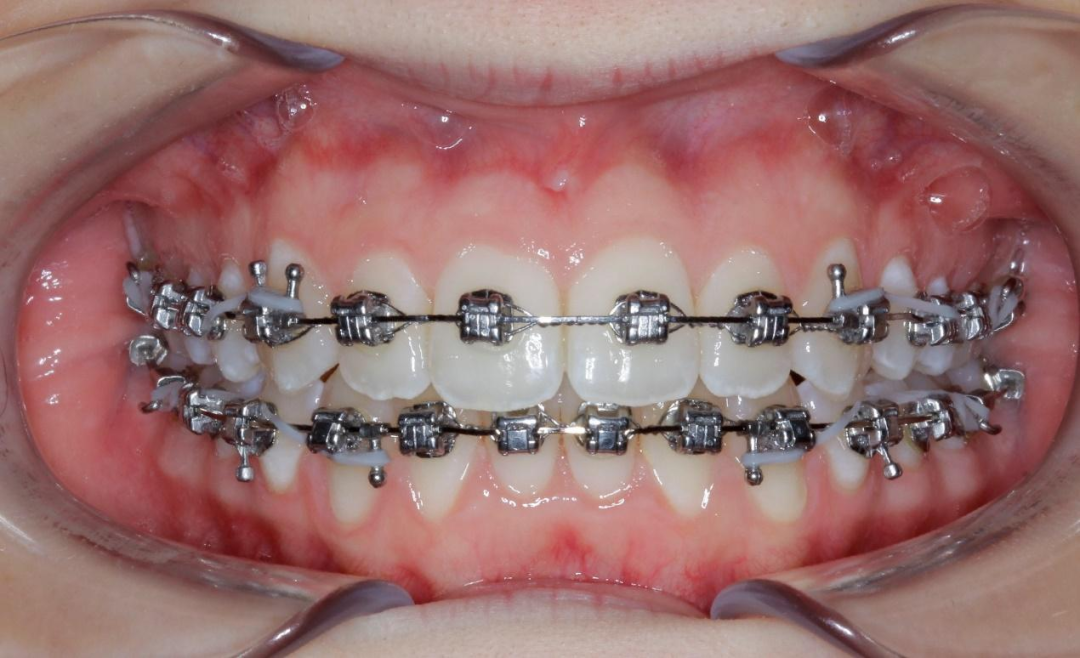

六、案例分享

8岁的乐乐,因长期口呼吸导致上牙弓狭窄。在楼凤网 人民医院,我们邀请耳鼻喉科会诊,帮助乐乐改善口呼吸问题后,为他佩戴扩弓器。经过6个月的治疗,不仅解决了牙弓狭窄的问题,口呼吸问题也一并得到了解决。看到乐乐自信的笑容,家长也松了一口气。